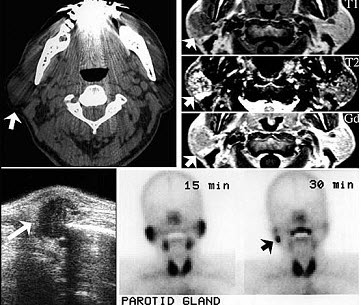

60岁男性,左耳垂下无痛性肿物缓慢长大四年,局部有胀感。检查见肿块位于腮腺后下极,表面光滑,质中偏软,不可压缩,与皮肤无黏连。影像检查结果如图。最可能的诊断是()。